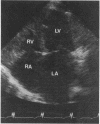

OBJECTIVE--To describe the association of the Noonan's phenotype and a primary, familial non-hypertrophic cardiomyopathy with restrictive pathophysiology. DESIGN--Observational study. SETTING--Tertiary cardiac referral centre. PATIENTS--Affected family members. METHODS--Two generations of a single family were examined and a description of the clinical characteristics and electrocardiographic, echocardiographic, and haemodynamic data of those affected is given. RESULTS--Three family members have classic Noonan's phenotype and all have a non-dilated, non-hypertrophic cardiomyopathy. Inheritance is autosomal dominant but with variable penetrance. The electrocardiograms show increased left ventricular voltages in two patients. On echocardiography left ventricular wall and internal end diastolic dimensions are normal, and there is considerable bilateral atrial enlargement. Systolic function is moderately impaired in one patient and mildly impaired in another. Doppler echocardiography showed restrictive pathophysiology as an early end of left ventricular filling and considerable reversal of flow in the superior vena cava during atrial systole. CONCLUSION--Hypertrophic cardiomyopathy is well described in Noonan's syndrome. This is the first report of a non-hypertrophic cardiomyopathy with echocardiographic and haemodynamic features of restrictive pathophysiology.